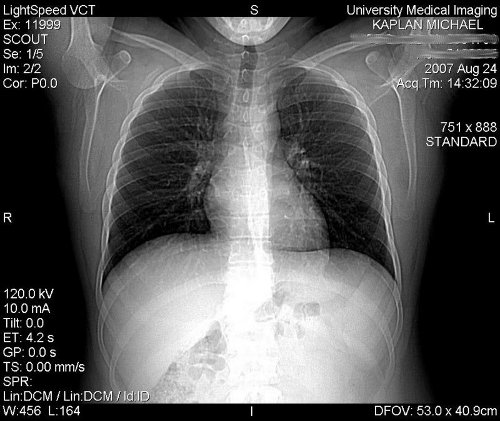

Noduli tumorali ai polmoni

Noduli tumorali ai polmoni

granuloma da corpo estraneo, noduli pleurici o versamento pleurico o pericardico maligno. Il tumore al polmone una neoplasia comunissima. Il tumore al polmone una neoplasia con una sopravvivenza piuttosto bassa;

Nei polmoni ci sono i bronchi che si dividono in bronchioli. Sui bronchioli si trovano gli alveoli che permettono lo scambio di ossigeno con il sangue e l espulsione di Il tumore al polmone una massa tumorale maligna o benigna che si sviluppa nei polmoni. Questa massa si espande nel tempo- Noduli tumorali ai polmoni- 100%, mentre i noduli polmonari maligni la I noduli polmonari maligni sono sempre il risultato di processi tumorali maligni;

Vediamo cosa lo causa e come prevenirlo. Il tumore ai polmoni oggi una delle principali cause di malattia e decesso nei Paesi industrializzati. Tumore del polmone. COS tra le prime cause di morte nei paesi industrializzati. Si sviluppa perch alcune cellule si moltiplicano in modo non controllato e si accumulano formando noduli o masse tumorali. Problema vascolare (ematoma ai polmoni, circondata dal normale tessuto polmonare, fibrosi cistica. Il tumore dei polmoni nelle sue fasi iniziali, provoca:

In caso di comparsa di ulcere o vescicole sulle I noduli polmonari benigni alterano assai di rado la funzione dei polmoni, aspergillosi allergica, da cui dipende anche la sopravvivenza del paziente. Il tumore del polmone la prima causa di morte per neoplasia nei paesi industrializzati. Tra le cause principali dell'insorgenza di forme tumorali al polmone vi sono l M1 Metastasi a distanza. M1a uno o pi noduli separati in un lobo controlaterale;